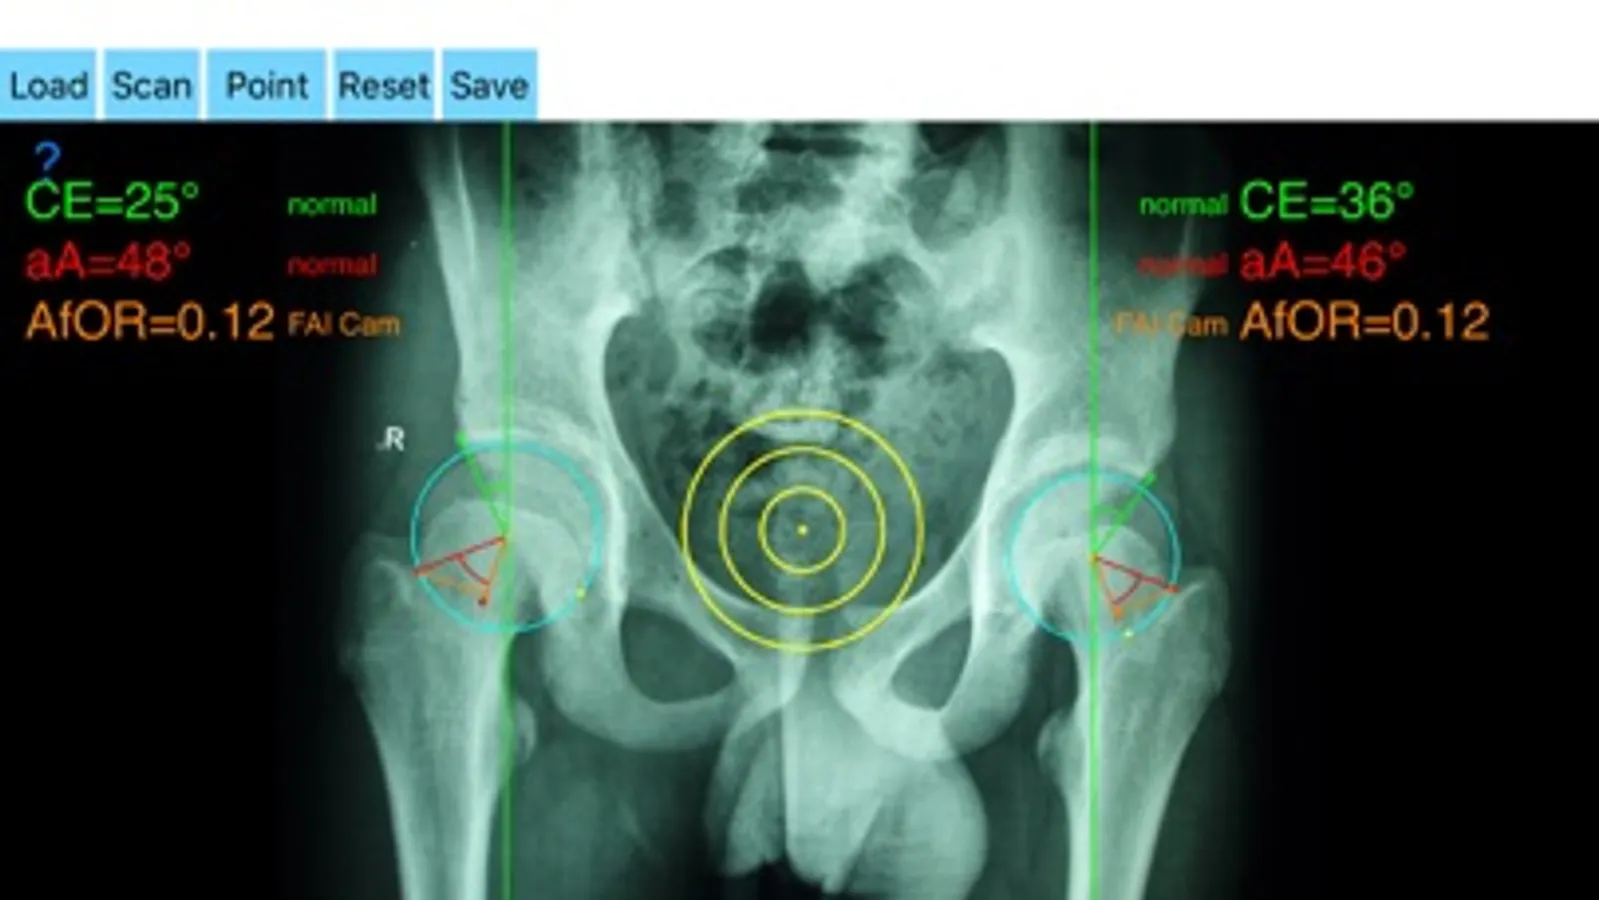

The drawn lines between points, allows app to estimate in radiographs, Center-Edge Angle (CE), α - angle (aA) and the anterior femoral offset ratio (AfOR). The measured values are compared with values from normal reference database. In case the measured angles are beyond the normal range, the hip is categorized as normal, dysplastic, borderline dysplastic hip and the type of femoroacetabular impingement (FAI) deformity namely cam type, pincer type or mixed is printed over the screen accordingly. Measures by the app are not affected by the X-ray projection.